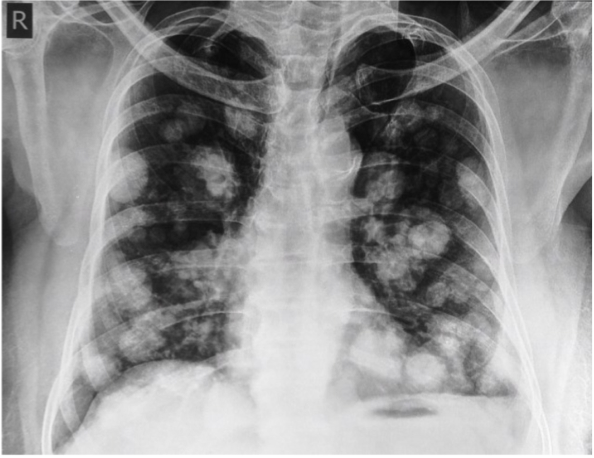

This shows diffuse pulmonary metastases, which _____ DPLD

This shows diffuse pulmonary metastases, which are not DPLD